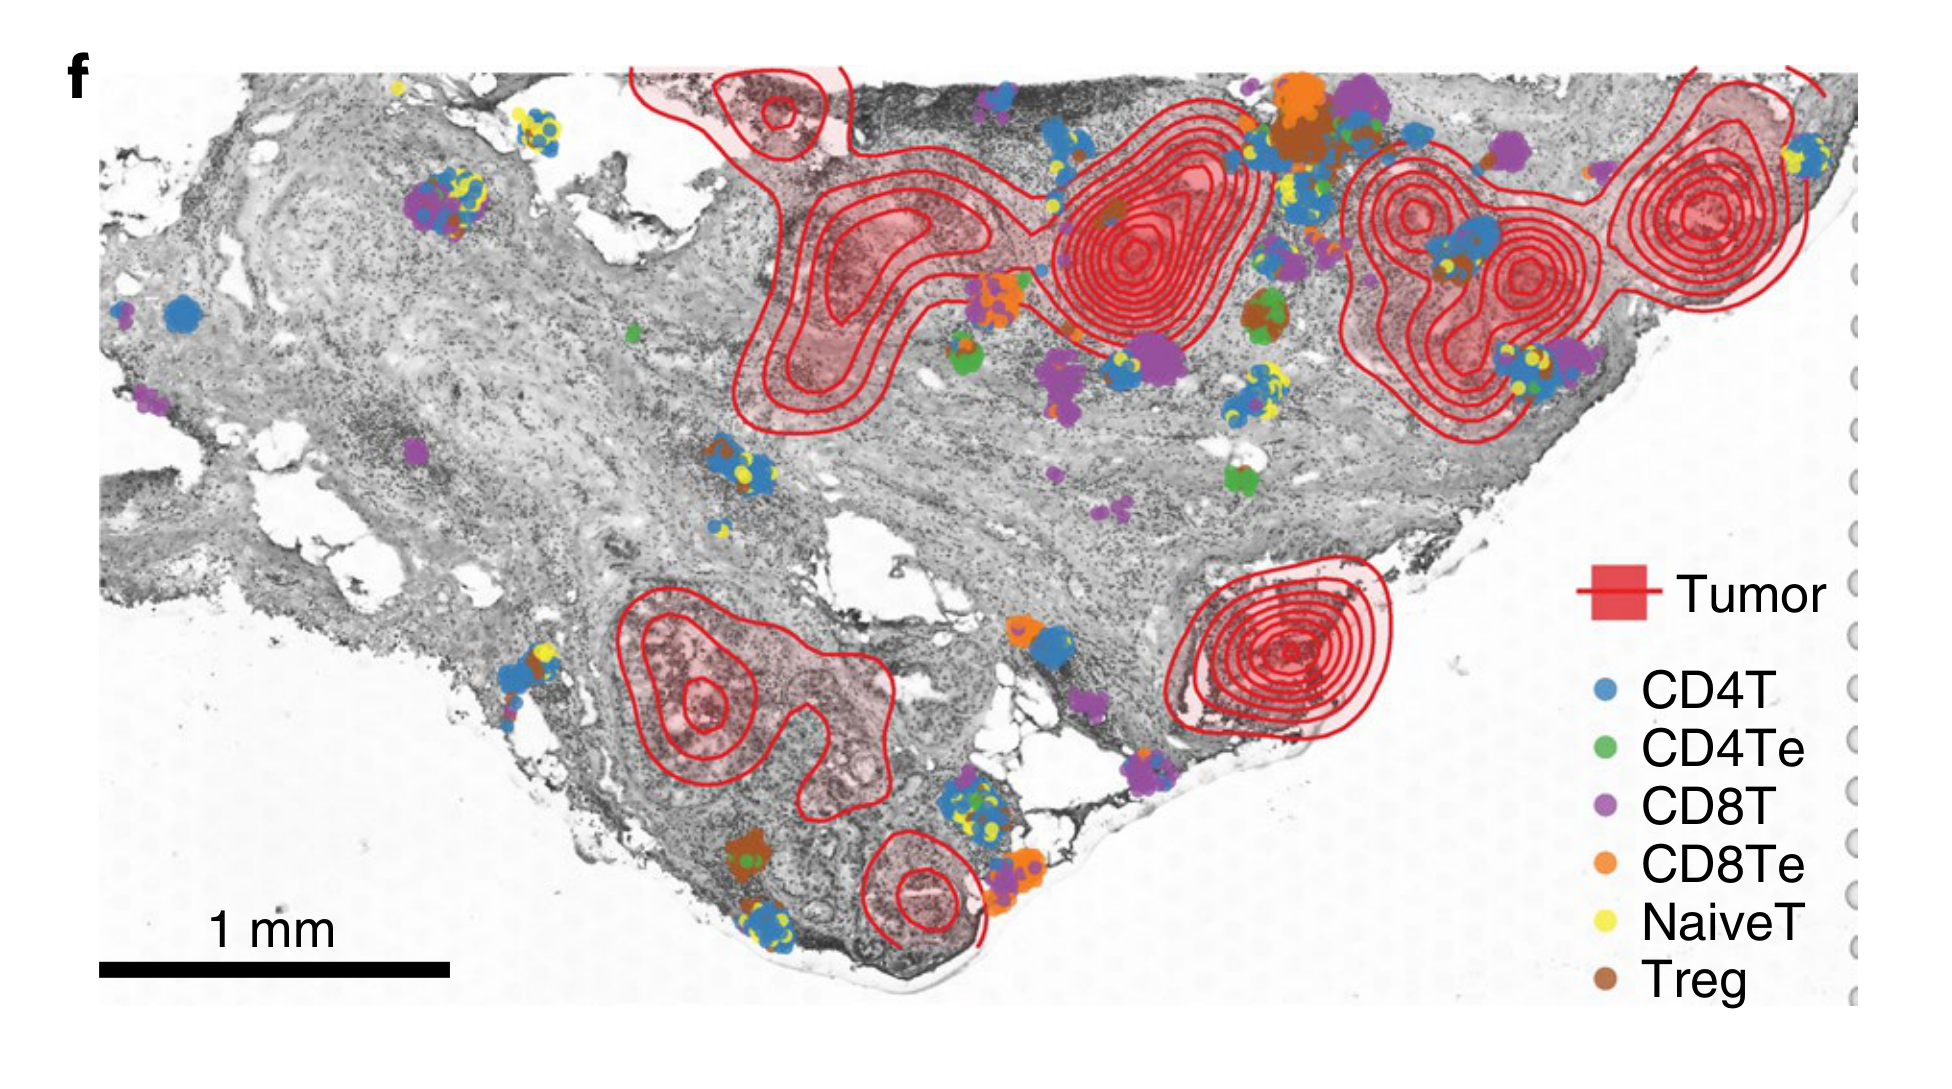

How are specific cell types spatially distributed across tumor tissue sections?

Annotation

None (Item-level)Sampling/Filtering